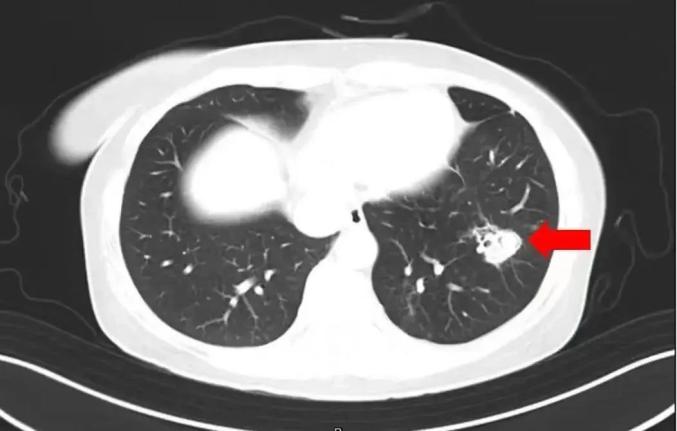

医生通过咨询了解到,沈女士在整理衣柜时发现里面有霉斑,于是清理了衣柜,但清洗时没有戴口罩。为了进一步诊断病情,医生对沈女士进行了纤维支气管镜检查和肺泡灌洗液病原体检查,发现气道内壁有大量白色菌斑,经检查确认为曲霉。